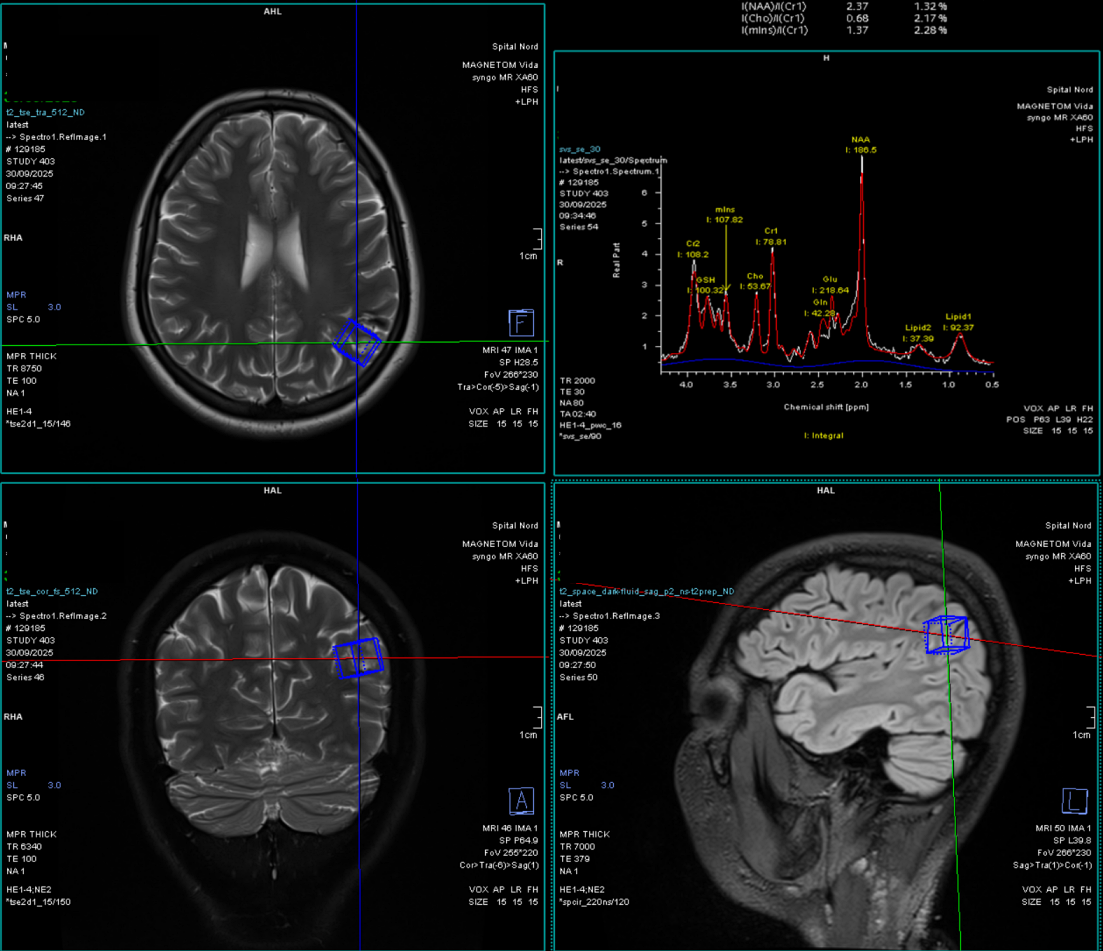

c) Spectroscopia RMN

- Oferă informații despre compoziția chimică a leziunii.

- Poate sugera dacă este vorba despre o tumoră malignă, un abces sau o leziune necrotică.